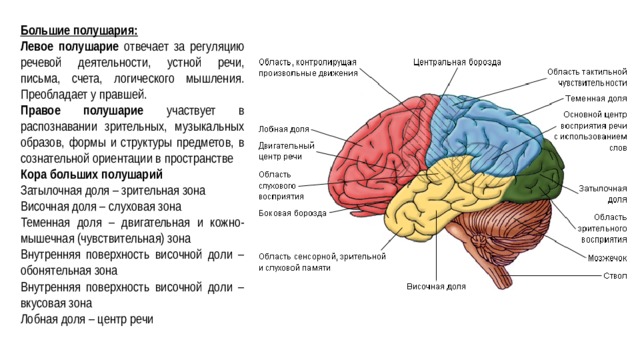

Схема чувствительных зон новой коры мозга